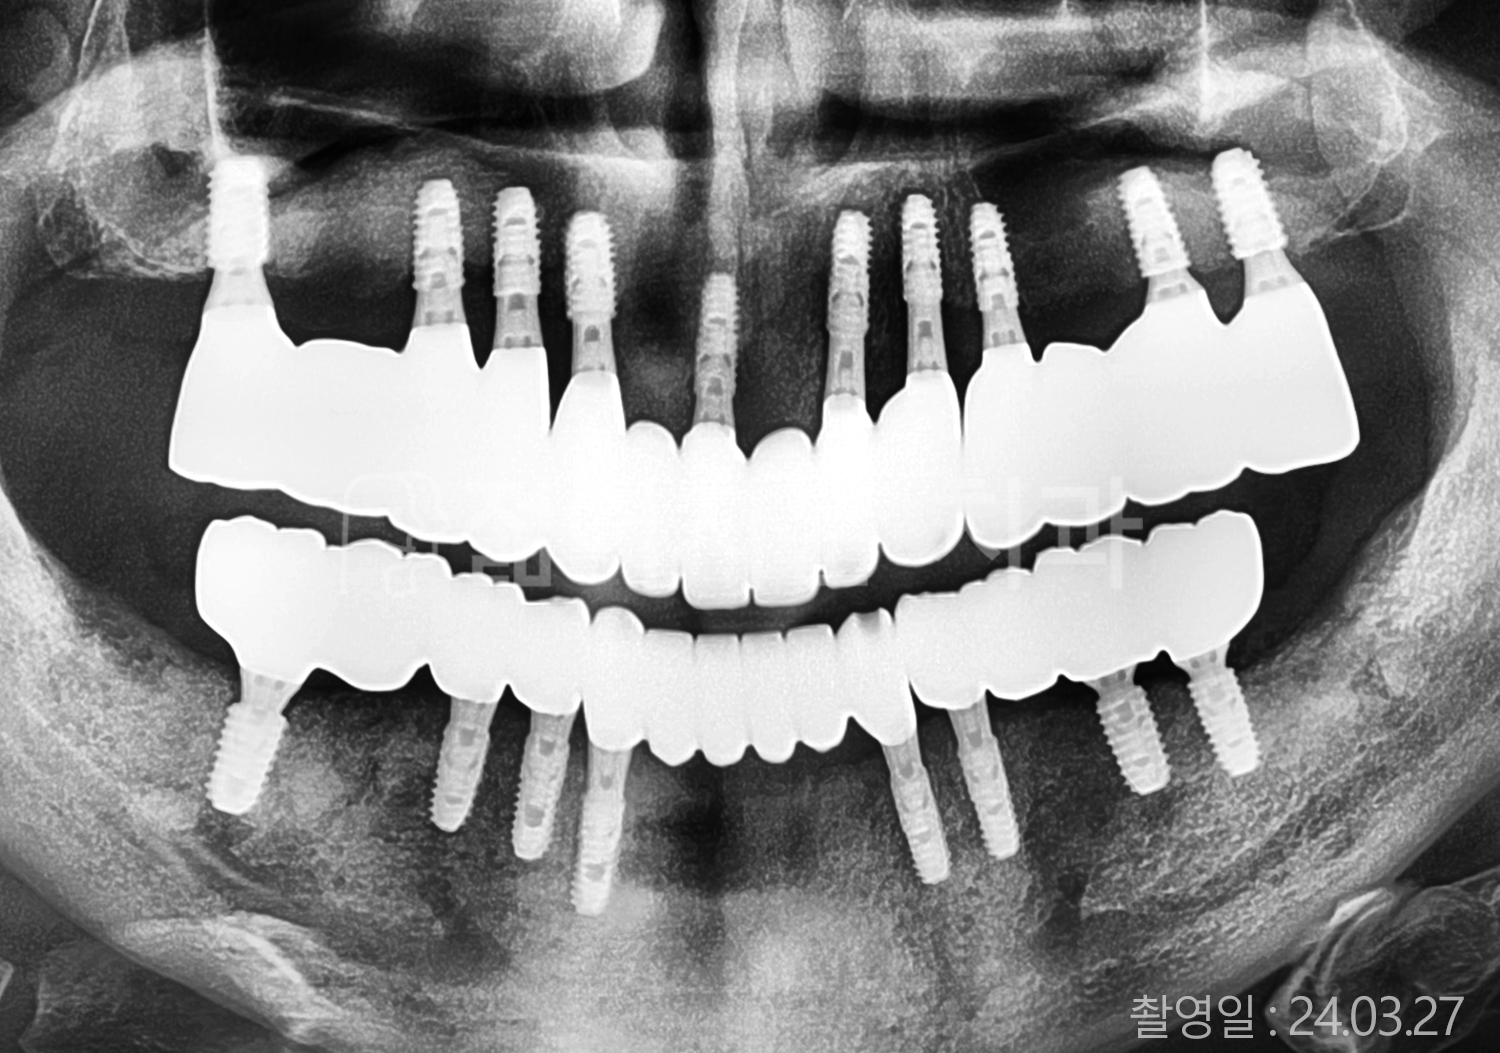

치료부위

식립개수

특이사항